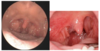

Ny information: Patienten behandles med fenoksymetylpenicillin 660 mg x 3 dagligt, men kommer igen efter 4 dage sammen med sin mor.Hun har opleves kortvarig bedring, men nu er synkesmerterne atter tiltaget, og hun har intet spist eller drukket 1 døgn. Smerterne sidder nu kun i den ene side og hun kan ikke åbne munden som hun plejer. Hun er igen højfebril og mor er meget bekymret. Hun har svært ved at åbne munden.

Ved inspektion af svælget ses som på nedenstående figur.

V: Hvad er den mest sandsynlige årsag til patientens symptomer på nuværende tidspunkt?

Peritonsillær absces

Billedet viser oropharyngeal asymmetri og ulvadeviation. Det er klassiske tegn på en peritonsillær abcess.

0-2 point

En 22-årig kvinde henvender sig til sin praktiserende læge med synkesmerter gennem 3 dage og feber. Her til morgen har hun målt sin temperaturen var til morgen 39,1 oC. Hun har drukket og spist sparsomt siden i går og er nu lettere alment utilpas. Der er ingen vejrtrækningsproblemer. Hun er tidligere i det væsentligste rask. For et par år siden oplevede hun dog symptomer der ligner de aktuelle.

Ved inspektion af svælget ses fund som i nedenstående figur. Der er hævede og ømme lymfeknuder bag kæbevinklen.

Ny information: Patienten behandles med fenoksymetylpenicillin 660 mg x 3 dagligt, men kommer igen efter 4 dage sammen med sin mor.Hun har opleves kortvarig bedring, men nu er synkesmerterne atter tiltaget, og hun har intet spist eller drukket 1 døgn. Smerterne sidder nu kun i den ene side og hun kan ikke åbne munden som hun plejer. Hun er igen højfebril og mor er meget bekymret. Hun har svært ved at åbne munden.

Ved inspektion af svælget ses som på nedenstående figur.

VI: Hvilke komplikationer kan opstå hertil?

- Para-/retropharyngeal absces (1)

- Abscederende lymfeknuder (1)

- Nekrotiserende fasciit (1)

- Lemierres syndrom (1)

En peritonsillær abcess skyldes ofte GAS (pyrogenes) eller fusobacterium necrophorum. Lemierres er en tilstand med fusobacterium necrohorum.

0-4 point

En 22-årig kvinde henvender sig til sin praktiserende læge med synkesmerter gennem 3 dage og feber. Her til morgen har hun målt sin temperaturen var til morgen 39,1 oC. Hun har drukket og spist sparsomt siden i går og er nu lettere alment utilpas. Der er ingen vejrtrækningsproblemer. Hun er tidligere i det væsentligste rask. For et par år siden oplevede hun dog symptomer der ligner de aktuelle.

Ved inspektion af svælget ses fund som i nedenstående figur. Der er hævede og ømme lymfeknuder bag kæbevinklen.

Ny information: Patienten behandles med fenoksymetylpenicillin 660 mg x 3 dagligt, men kommer igen efter 4 dage sammen med sin mor.Hun har opleves kortvarig bedring, men nu er synkesmerterne atter tiltaget, og hun har intet spist eller drukket 1 døgn. Smerterne sidder nu kun i den ene side og hun kan ikke åbne munden som hun plejer. Hun er igen højfebril og mor er meget bekymret. Hun har svært ved at åbne munden.

Ved inspektion af svælget ses som på nedenstående figur.

VII: Angiv mulige behandlingsmetoder?

- Enten aspiration, incision og antibiotika (1)

- Eller tonsillectomi a chaud (1)

En perisontillær abcess behandles ved ØNH, hvor den enten tømmes og patienten får antibitoika ELLER tonsillen med abcess fjernes.

0-2 point